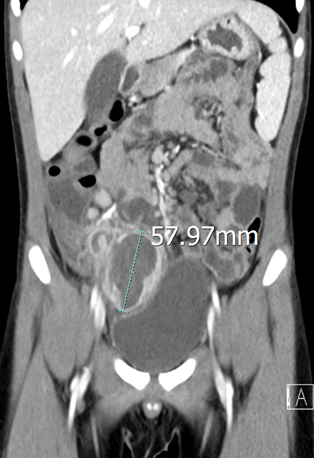

보통 lapa로 하는데 특이하게 이번에는 open으로 했다.(소아)

에 나오는 mcburney 지점을 incision 했다.

역시 open으로 하는거라 훨씬 간단하긴 하다. 다만 incision 부위를 작게해서 보는데 불편함이 약간 있어 보였다.

1. #15 mess incision on mcburney